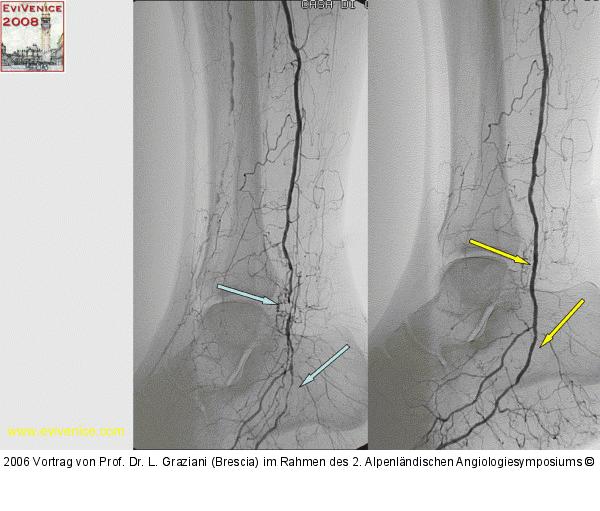

Vortrag von Prof. Dr. L. Graziani (Brescia) im Rahmen des 2. Alpenländischen Angiologiesymposiums

PTA of the foot arteries in diabetics: Extremities Extreme Angioplasty

Abbildung 23: Revaskularisation